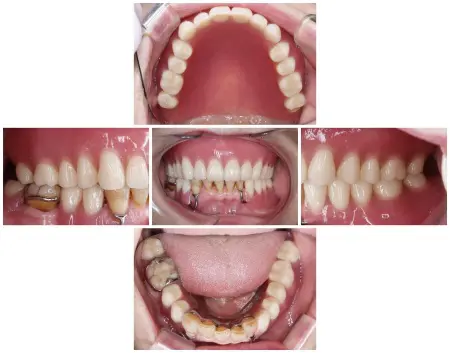

理想的な歯並びと噛み合わせになるように最終的な入れ歯を設計し、患者様のご希望も丁寧にうかがったうえで歯の色や形を決定しています。

後日、完成した新しい入れ歯を上下顎にそれぞれセットし、しっかり噛めることを確認してから治療を終了しました。

現在は、ご自宅での歯磨きにきちんと取り組んでいただくとともに、定期的なクリーニングと経過観察で通院いただいています。